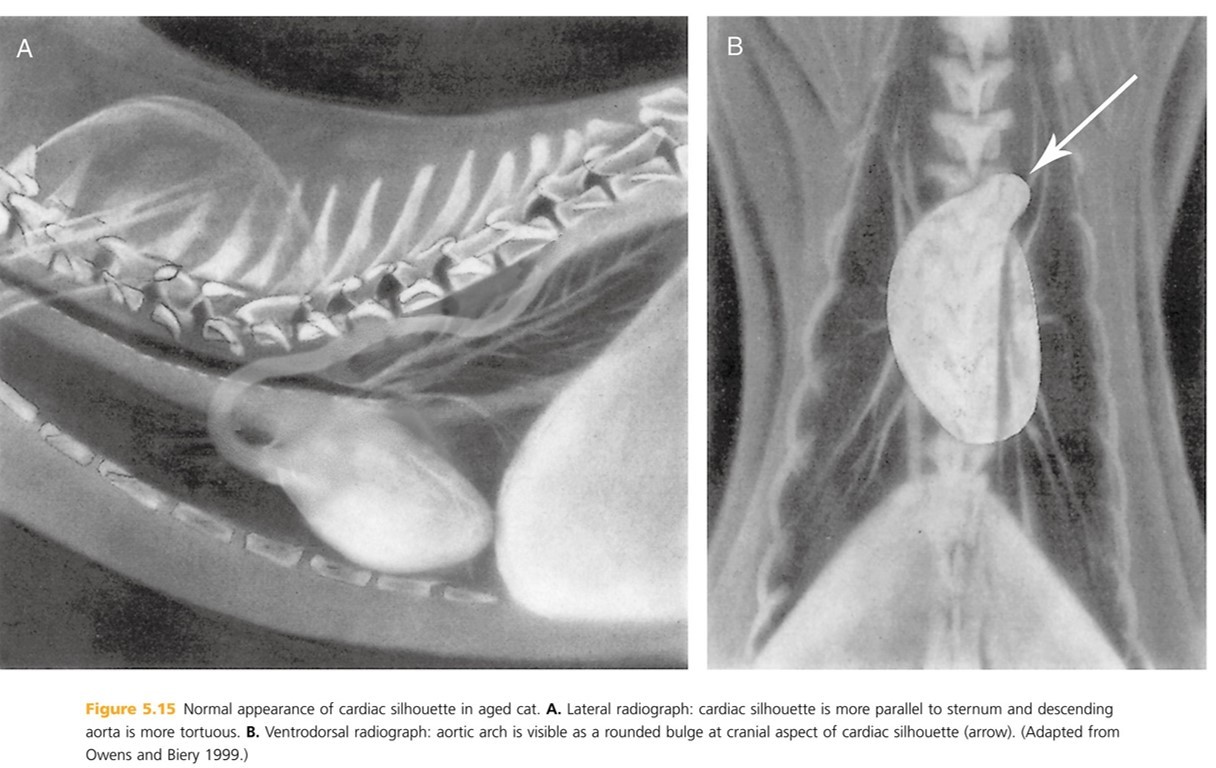

Older cats loose the elasticity of the aortic wall resulting in an altered appearance to cardiovascular structures. The heart moves more ____ to the sternum and the aortic arch b/c more prominent (described as “____” or “_____”) and may be mistaken for a cranial mediastinal or pulmonary mass on (_____ radiographs). On _____ radiographs, the desecending aorta appears more tortuous, wavy , or redundant

parallel

Kinked or knuckled

VD/DV- (B)

lateral - (A) BTW, hypertension can also result in a more tortuous descending aorta